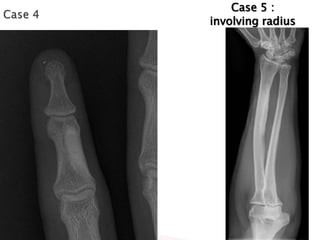

Case 5 :

involving radius

•May be monostotic or polyostotic

•May involve one entire limb

•Usually does not involve multiple limbs

It has a predilection for long bones of the limbs ,it can be seen

almost anywhere

Sclerotic lesions of cortical bones, usually in the diaphysis,

that resemble “candle-wax-dripping”

Cortical hyperostosis with an undulating appearance usually

affecting one side of a bone